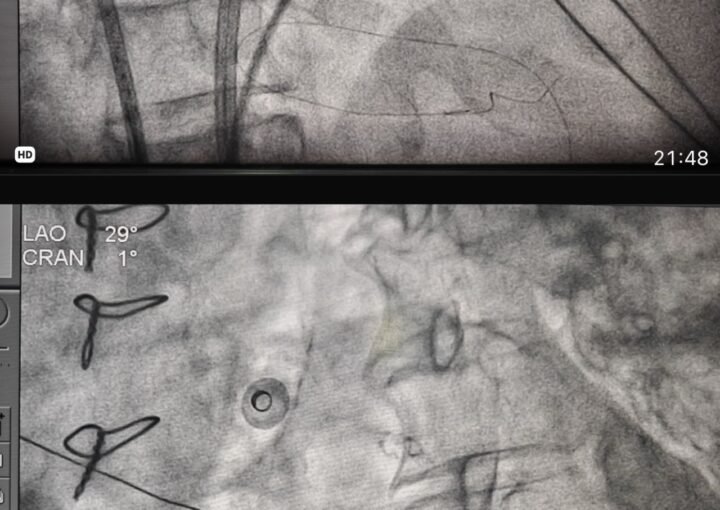

Aster_Ace_Super_Admin November 17, 2025 Post MVR LA flutter ablation: rewarding procedure for heart failure